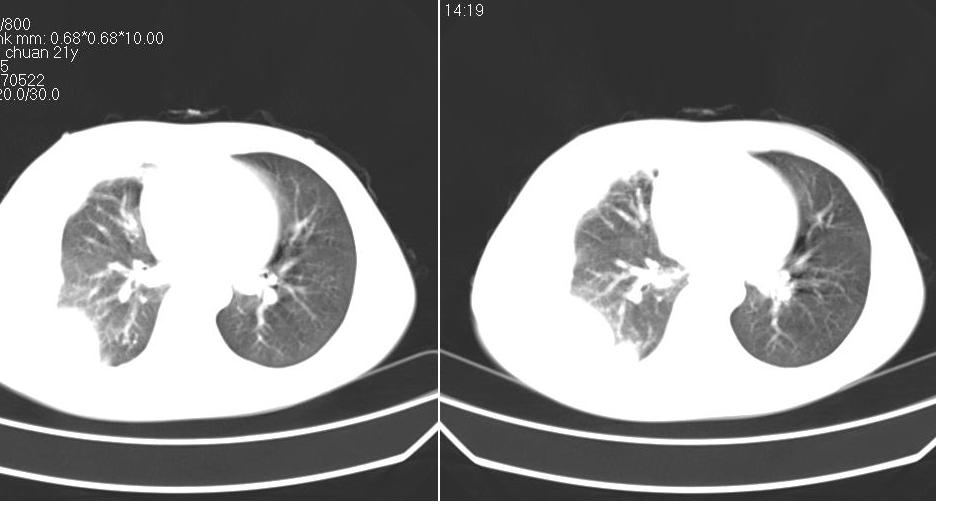

男 21岁,胸闷。

右侧包裹性积液(结核性可能大)。

右侧胸腔积液,部分呈垂滴状,包裹了,最常见的原因是结核引起的

右侧包裹性胸腔积液,考虑1:结核,2:胸膜间皮瘤